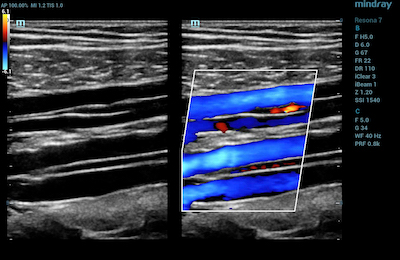

- Blood Vessels – Vascular ultrasound is used to evaluate the circulatory system. CDI is used to diagnose and stage acuity of clots in the veins, as well as venous reflux. It is also useful to assess narrowing and blockages within a patient’s arteries.

Color Doppler of Posterior Tibial and Peroneal Veins in the calf